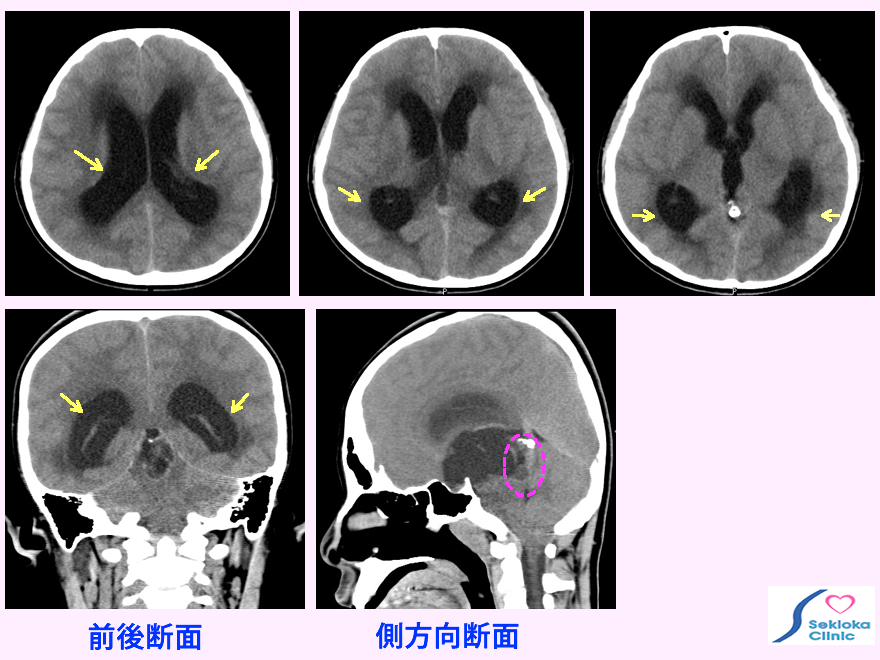

CT, MRI。本例は画像中、矢印で示す如く側脳室、第3脳室の著明な拡大、側脳室前・後角周囲の浮腫を認め(黒い部分)、水頭症を生じている。その原因は松果体腫瘍(ピンク色破線)が正常な髄液の流れを障害して生じていた。